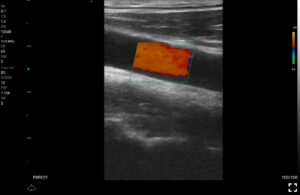

Παραδείγματα

Ολες οι παραπάνω απεικονιστικές εξετάσεις έχουν ληφθεί από φορητή συσκευή όπως: Apple Iphone, Tablet, Samsung Mobile Phones και διάφορες άλλες φορητές συσκευές.

Παραδείγματα Video